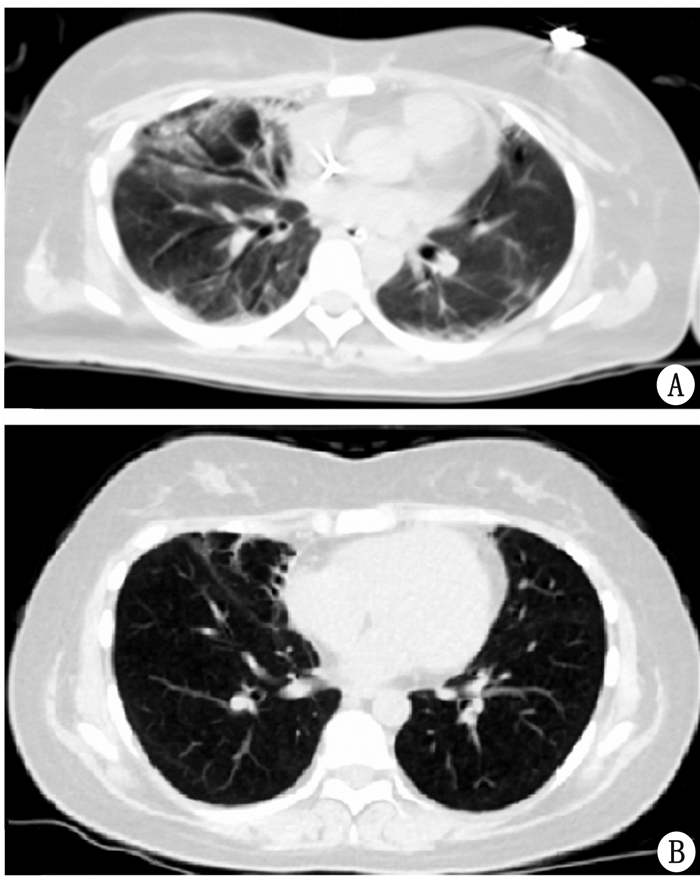

病例2患者,女,17岁,此次患病前身高157 cm, 既往患抑郁症1年余,因“误服药物后意识障碍、呼吸困难13 d”于2017年4月28日入院。2017年4月15日因误服抗精神病(具体名称及剂量不详)后出现意识障碍,轻度躁动,言语混乱,约30 min后送至当地医院给予洗胃,意识障碍仍加重,呼吸困难伴低氧血症,立即给予气管插管接呼吸机辅助呼吸,血液药物浓度检测示:喹流平1.3 μg/mL,文拉法辛1.1 μg/mL,米氮平0.6 μg/mL,给予“氟马西尼、纳美芬、哌拉西林他唑巴坦针”及维护器官等对症支持治疗,患者意识渐转清,4月18日患者出现意识障碍再次加重,呼吸无力、氧饱和度下降,复查胸部CT、感染指标提示双肺炎症加重,更改抗生素为“美罗培南、万古霉素”,感染指标稍好转,但呼吸困难加重、呼吸机支持(控制通气,潮气量500mL,PEEP 18 cmH2O,FiO2 80%)加大的情况下SpO2仍然难以维持在90%以上;4月26日颈部及前胸部出现皮下气肿,给予“左侧锁骨下皮下气肿切开引流术+气管切开术”,进一步调整呼吸机参数、增强呼吸支持后,SpO2维持在90%左右,但渐出现血压下降,需应用升压药维持血压,心率140次/min左右;急请我院会诊考虑存在重症肺炎、急性呼吸衰竭、ARDS,我急诊重症医师及ECMO团队,给予救护车上ECMO应用下转运至我院。入院后查体:患者神志昏迷,GCS评分E3VTM5,气管切开接呼吸机辅助呼吸(压力控制通气,PEEP 10 cmH2O,FiO2 60%,呼吸频率15次/min,PC above PEEP 15 cmH2O),监测潮气量180 mL左右,ECMO应用下SpO2维持在95%左右,颈部及胸壁皮肤有握雪感,左锁骨下方有一长约5 cm横行纱布覆盖切口,双侧瞳孔等大等圆,直径3 mm,对光反射迟钝,呼吸运动减弱,双肺呼吸音明显降低,未闻及干湿啰音,心率120次/min,律齐,余心脏、腹部、神经系统未见明显异常;入院后化验示:PaO267.1 mmHg,PaCO242.0 mmHg;白细胞数26.70×109/L; PCT2.380 ng/mL;白蛋白23.7 g/L;BNP3 797.0 pg/mL;胸片示:两肺纹理增粗,肺内多发大片状高密度影(图 3A);患者肺功能极度衰竭,持续ECMO应用(转速3 000转/min,氧流量5 L/min)替代肺功能,下调呼吸机调节参数、严格控制气道压30 cmH2O以下、防止肺部气压伤加重,PEEP 10 cmH2O左右维持肺开放,并给予“美罗培南、利奈唑胺、伏立康唑”抗感染、低剂量阿奇霉素、甲泼尼松龙防止肺纤维化及保护脏器等对症支持治疗,至5月5日PaO2逐渐上升为93.7 mmHg;PaCO241.4 mmHg;白细胞数8.50×109/L; PCT为1.500 ng/mL,白蛋白41.9 g/L;但潮气量上升不明显,200 mL左右,肺顺应性仍极差;5月9日患者右侧胸腔出现气胸,气胸量约75%,行“右侧胸腔闭式引流术”,5月12日观察胸腔闭式引流管中无气泡引流后给予拔除,氧合及胸片可见肺部情况渐好转,肺顺应性改善,潮气量逐渐升为400 mL左右,氧合指数大于300 mmHg, 5月20日给予逐渐下调ECMO氧流量,患者动脉血氧分压无明显下降,5月21日ECMO应用23 d后给予撤离。5月22日复查胸片肺部炎症明显改善(图 3 B),胸部CT示:双肺间质性改变(图 4 A );患者呼吸情况好转,逐步降低呼吸机支持并于5月28日脱机,后好转出院,随访(出院5周后胸部CT见图 4 B)至今无明显不适。

| A为ECMO撤机后查胸部CT情况 B为出院后5周随访CT 图 4 患者2ECMO撤机后CT片 |